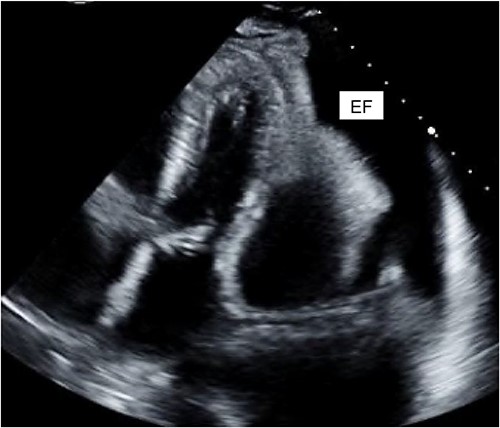

A 40-year-old female with a history of IV drug use and liver dysfunction presented with MRSA bacteremia and spontaneous bacterial peritonitis. Despite intravenous antibiotics and supportive measures, the patient’s clinical status worsened eventually proceeding to a pulseless electrical activity arrest. Following successful resuscitation and transfer to high acuity care, cardiac echocardiography (ECHO) revealed significant mitral and tricuspid valve regurgitation suggestive of infective endocarditis (IE). Unfortunately, the patient developed both kidney and liver failure and these factors along with a poor clinical status precluded surgical intervention at that time. Despite broad-spectrum intravenous antibiotics the patient remained persistently febrile with an elevated leukocyte count. Further analysis of blood cultures identified gross candida and addition of IV antifungals led to a marked clinical improvement. Despite this, the patient again worsened and cardiac ECHO revealed a loculated pericardial effusion, with significant compression of the right atrium and both ventricles, suggestive of cardiac tamponade (Fig. 2). The patient was promptly taken to the operating room, a pericardial window made and 450 cc of purulent fluid drained (analysis confirmed the presence of candida), the pericardium was washed with warm sterile water and a 20-French chest tube placed. Intravenous antibiotics and anti-fungal medications were administered thereafter.

Cardiac ECHO images: ECHO images of the patient’s heart. EF represents effusion.